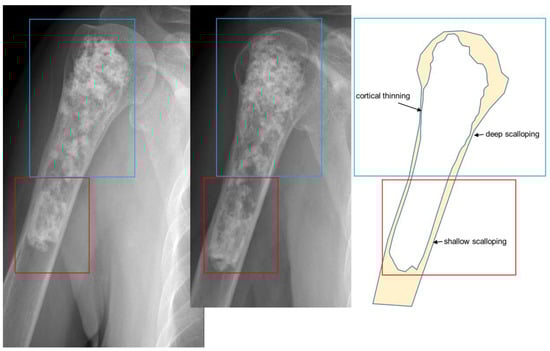

3.1. Distinction between Enchondroma and ACT

3.2. Biopsy or Follow-Up? Questions for Incidental Cartilage Lesions in the Long Bones